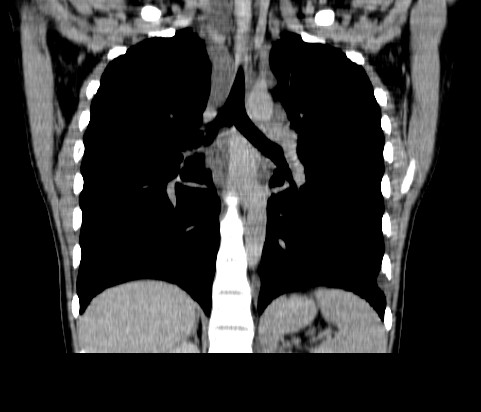

胸部